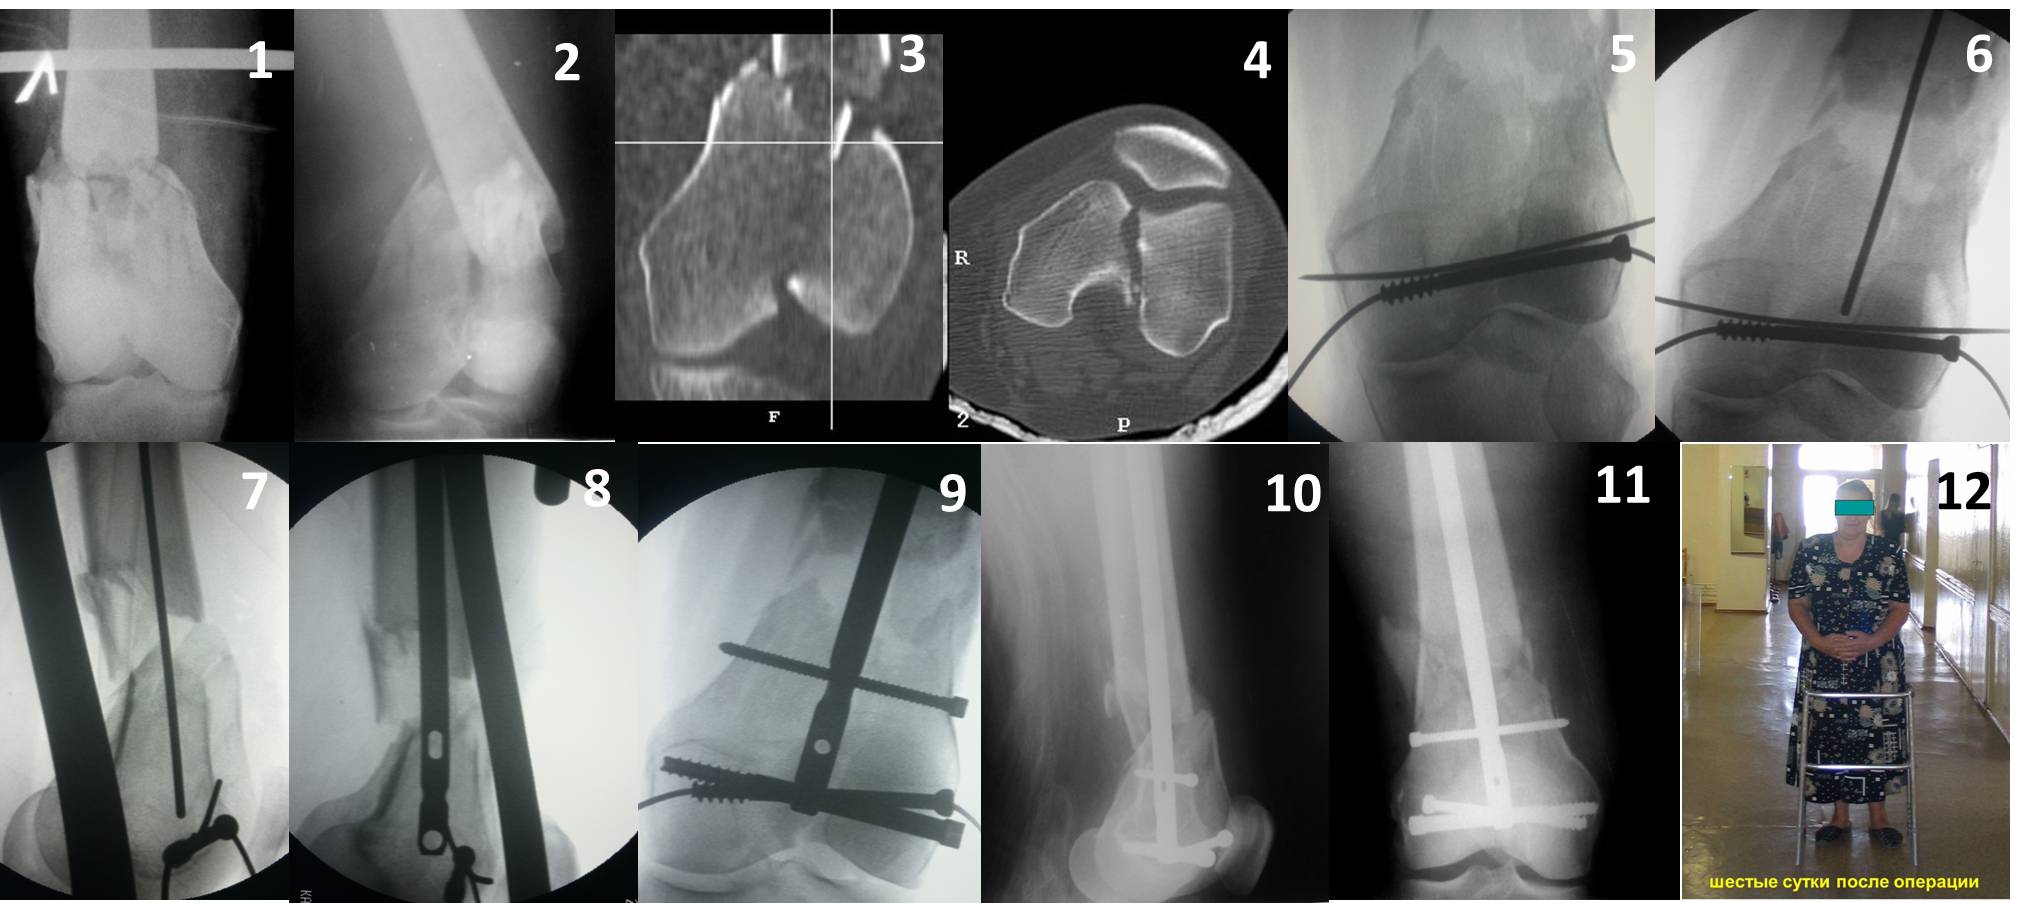

Ну зачем же так. Всё-таки считается "золотым стандартом". Во вложенном файле коллаж из сохранившихся фотографий одной из операций. Всё сделано закрыто и без ЭОПа.

|